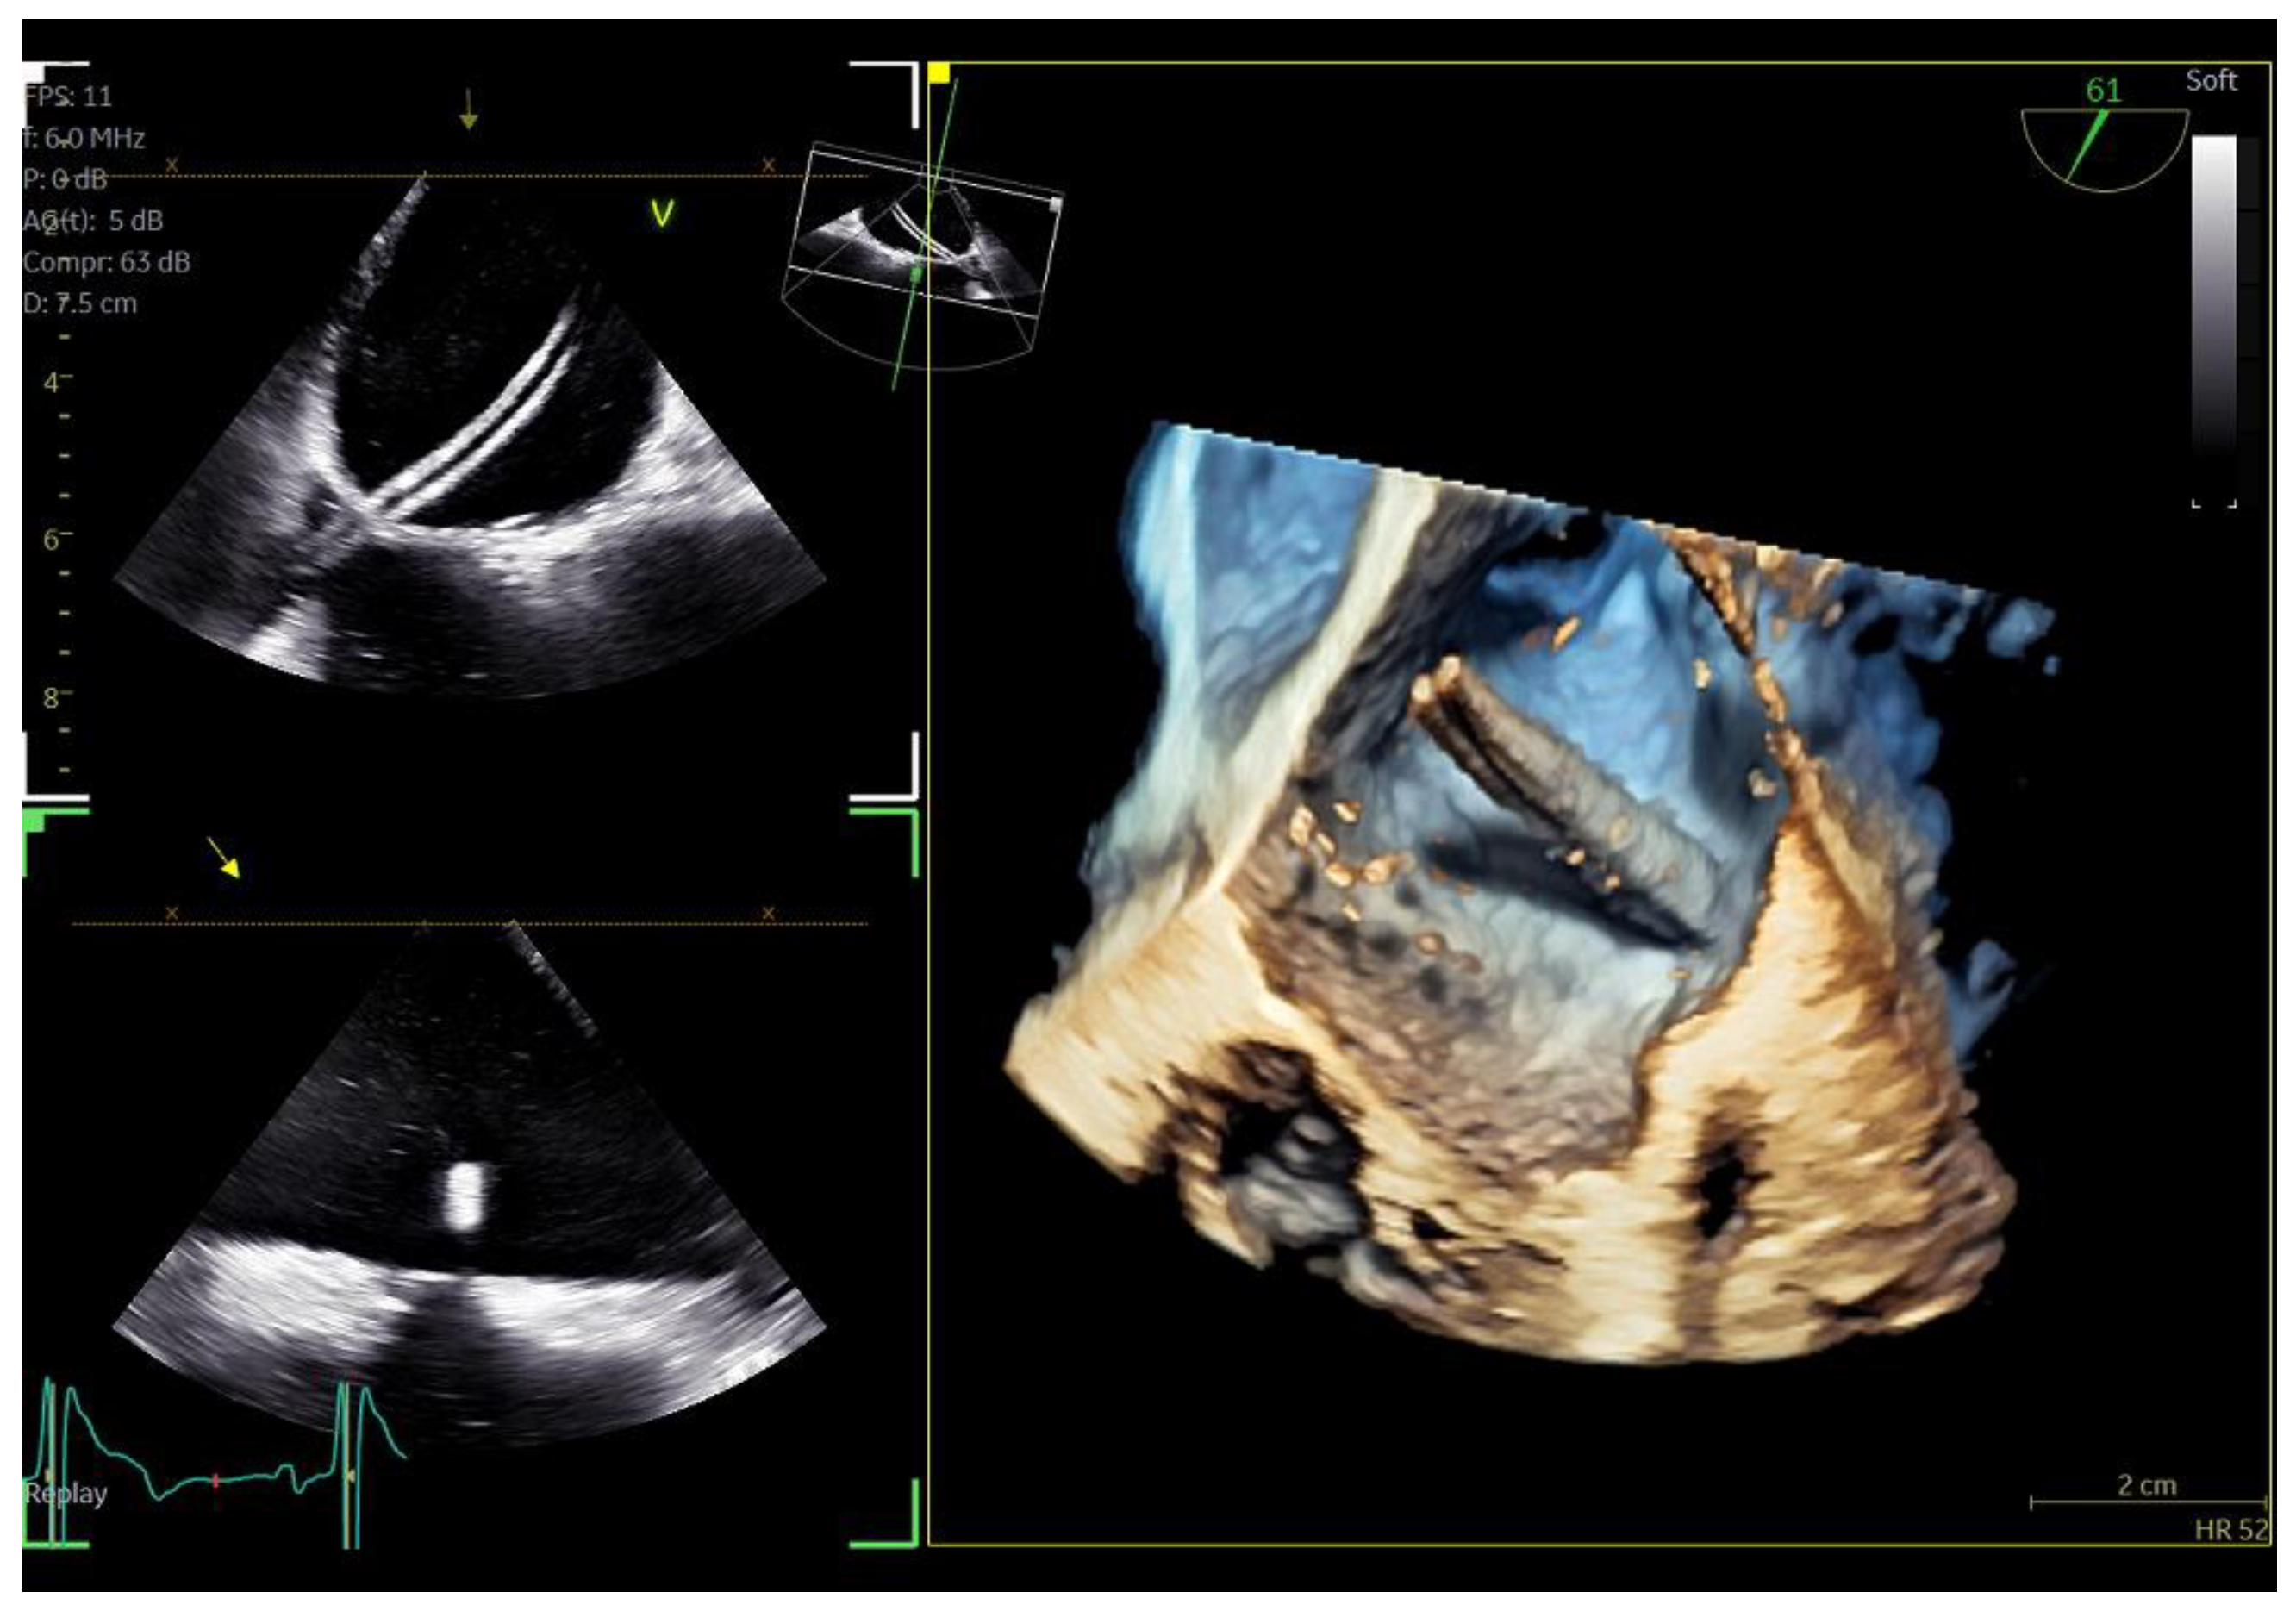

Figure 1.

Direct comparison of 3D volume −rendered “en face” images of a metallic prosthetic mitral valve with occluded disk. Left image corresponds to 6VT−D adult probe and right image corresponds to 9VT−D pediatric probe.

The quality of images obtained with the 9VT-D pediatric probe and the accuracy of findings were assessed through examination of the first three patients. Each patient underwent a comprehensive TEE protocol using both the pediatric 9VT-D and adult 6VT-D probes, allowing for direct comparison of findings and image quality. Throughout the procedure, patients received local oropharyngeal lidocaine and mild sedation with midazolam to ensure tolerance.

The adult probe was initially inserted for complete 2D/4D image acquisition, followed by the insertion of the pediatric probe while the patient remained under sedation. Remarkably, insertion of the pediatric probe was effortless in all cases, requiring no additional sedation. Despite encountering challenging diagnostic scenarios in all three cases (1st patient: combined severe aortic stenosis and severe mitral regurgitation (MR) due to P1 scallop prolapse, 2nd patient: malfunction of metallic mitral valve prosthesis with an occluded disk, 3rd patient: bioprosthetic aortic valve with paravalvular leak and significant MR in previously MV repair with a complete ring), the pediatric probe consistently provided high-quality images comparable to those obtained with the standard adult probe (Figure 1 and Figure 2, video S4). Notably, there was no compromise in 2D and 4D spatial and temporal resolution, with only minor differences observed compared to the adult 6VT-D probe (Table 1). Evaluation using the 5-point scoring system consistently yielded an average score close to 5 for all three cases, indicating excellent image quality (Table 1).